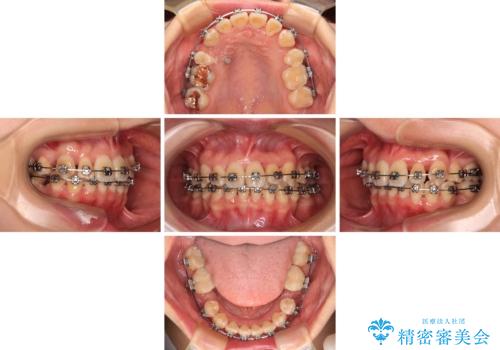

【モニター】前歯のデコボコをワイヤーの抜歯矯正で綺麗に整える

- 前歯1本が後ろ側に隠れてしまうほどのデコボコを気にして来院された患者様です。

前歯のデコボコが顕著なのはもちろんですが、左右ともに奥歯の咬み合わせに問題があり、上顎臼歯が前方位にある状態でした。

上顎は左右の第一小臼歯2本を、下顎は左右第二小臼歯2本を抜歯することで、奥歯の咬み合わせを改善しながら、デコボコを解消していくこととしました。

- 矯正装置

- メタルブラケット